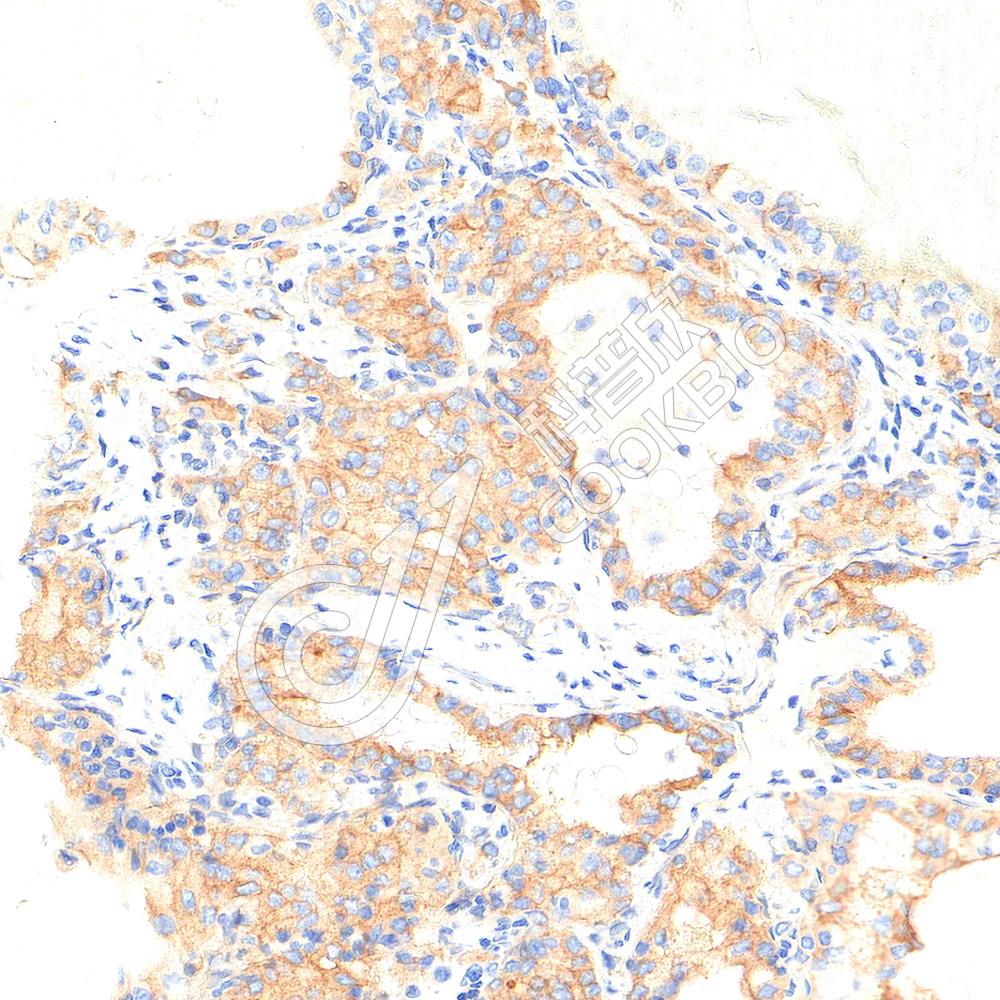

IHC检测AMPK alpha 1蛋白(货号 K5450072).

样品: 人结肠癌, 4%多聚甲醛 (货号KSG1101) 固定12-24小时.

抗原修复: Tris-EDTA抗原修复液(pH 9.0) (KSG1203), 98℃, 20分钟.

—抗: 1: 600稀释, 4℃ 孵育过夜.

二抗: S-vision免疫组化多聚二抗(山羊抗兔),即用型 (货号KB3906), 室温孵育20分钟.

样品: 人肾癌, 4%多聚甲醛 (货号KSG1101) 固定12-24小时.